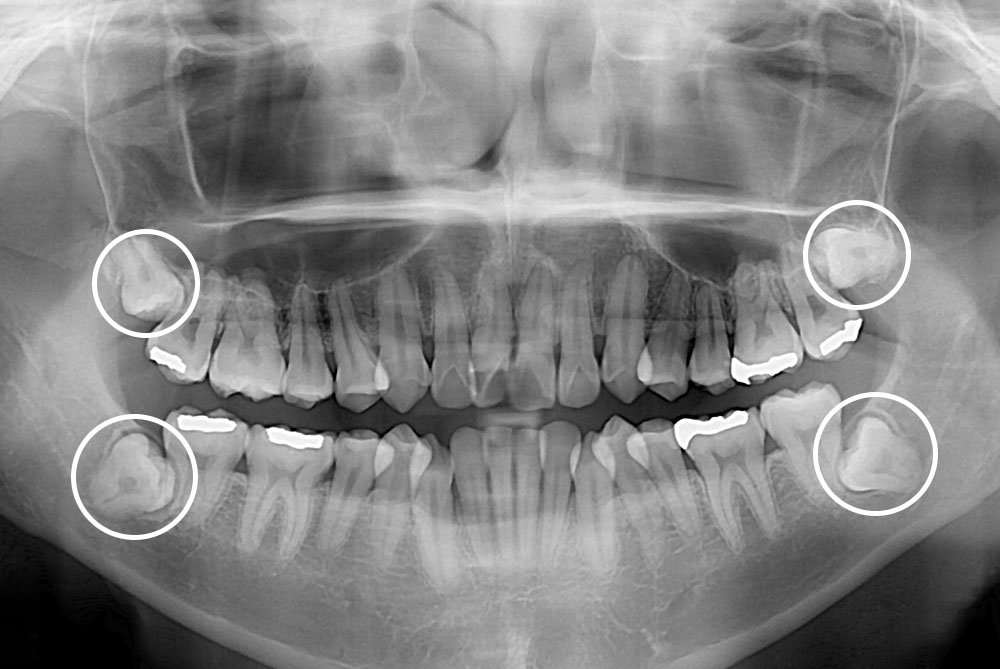

[사랑니] 매복 사랑니 발치

치료전 : 2019-04-23